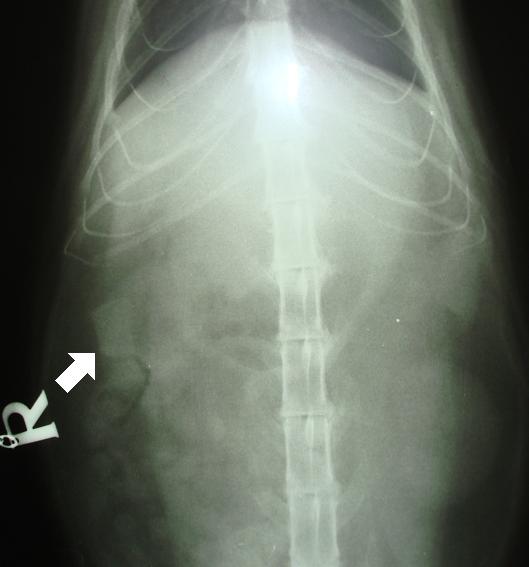

Na následující fotografii je předozadní rentgenologický snímek dutiny břišní. Bíla šipka ukazuje na cizí těleso v tenkém střevě. Na snímku je vidět, že cizí těleso není nijak výrazné, jako například kostěná tkáň obratlů. Díky svému složení má cizí těleso na RTG snímku odstín (opacitu) šedi  jako okolní měkká tkaň. Je možné, že kdyby se nacházelo v jiné části střeva, nebylo by vůči okolním tkáním dostatečně kontrastně vykreslené. Proto by se dalo lehce přehlédnout. Většina pozřených cizích těles je z plastu, gumy a různých tkanin. Tyto materiály mají na RTG snímcích vzhled (opacitu) okolní  měkké tkáně. Proto nám je rentgenologické vyšetření často nemusí odhalit nebo podává pouze podezdření na jejich přítomnost v trávícím traktu.

RTG-CT-špunt do ucha